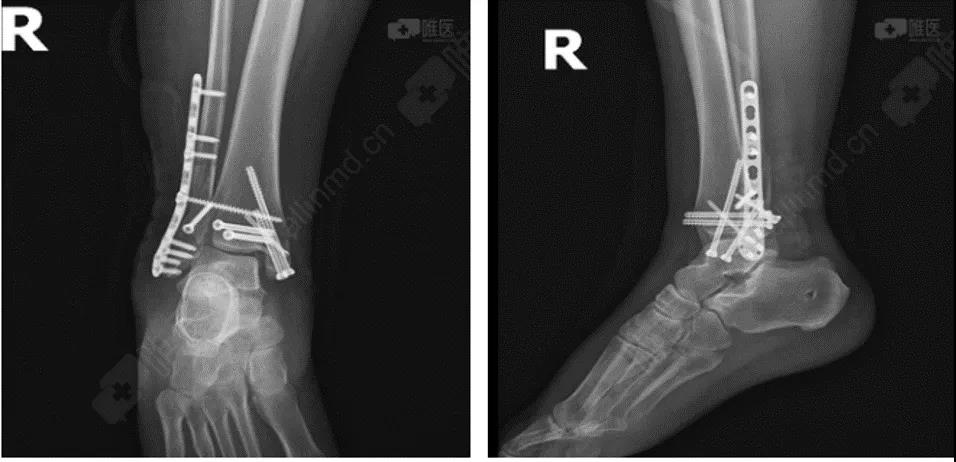

术后DR

术前DR